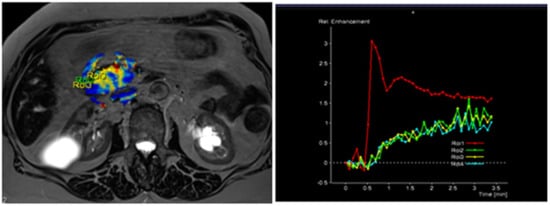

The radiological findings were compared with histopathological data. Histopathological analysis was performed at the Department of Pathological Anatomy, Lithuanian University of Health Sciences. The study patients were further grouped according to the differentiation grade (G value): well- and moderately differentiated (G1 + G2) and poorly differentiated (G3) PDAC. Images of DCE-MRI of non-tumorous pancreatic tissue and PDAC are presented in Figure 2 and Figure 3.

Figure 3. MRI perfusion images of G3 tumor in the head of the pancreas with TSIC—type II (slow enhancement and then continuous enhancement). The curve graph shows that pancreatic tumor enhances to a lesser extent than surrounding nontumoral pancreatic tissue. Most poorly differentiated (G3) tumors showed Type II pattern enhancement.